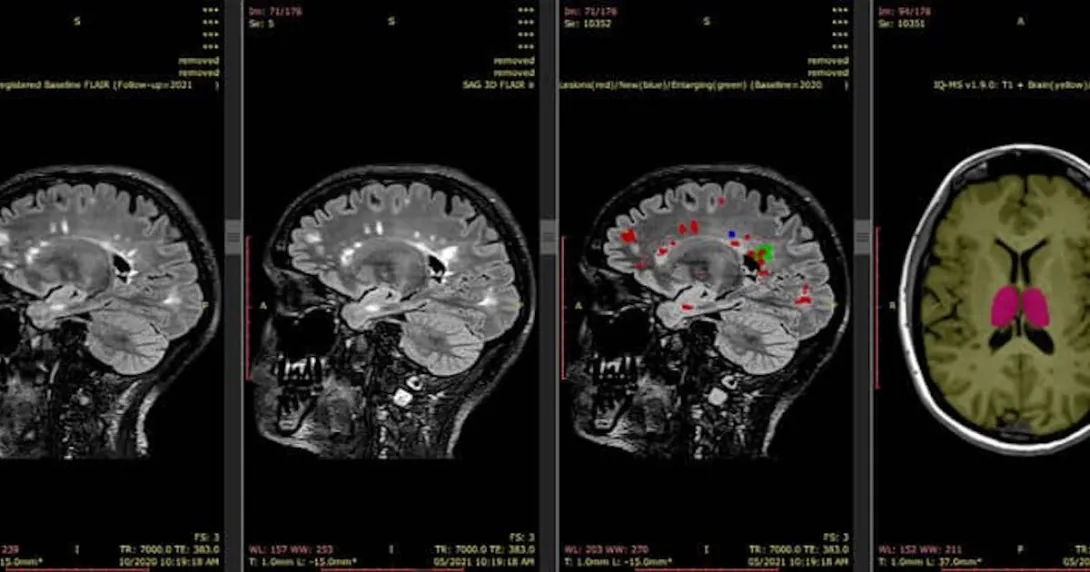

The funding will help scale and accelerate the commercialisation of its AI-enabled medical imaging software. iQ-solutions provides quantitative analysis of brain structures from MRI scans. It enables the precise and personalised monitoring and management of brain diseases, including multiple sclerosis and dementia.

"Our flagship tool, iQ-Solutions, supports radiologists to improve the detection and quantitation of new brain inflammation in patients with multiple sclerosis, which may prompt clinicians to recommend a change in therapy to prevent future disability," explained Michael Barnett, University of Sydney professor and co-founder of SNAC.